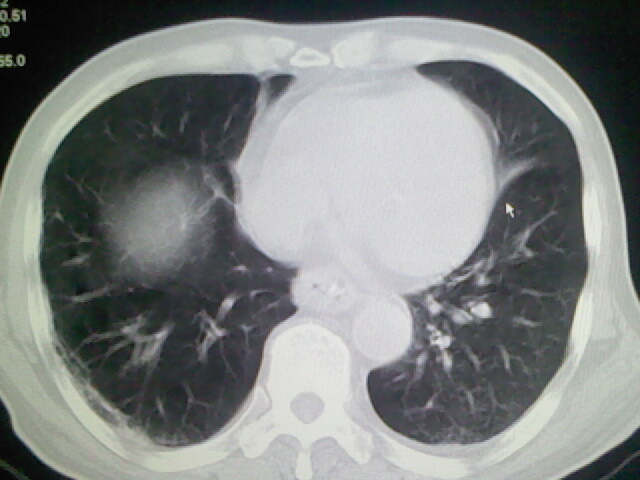

男,70岁,脑出血,长期卧床,左侧背部可触及肿块

右肺病灶考虑炎症性。

右肺病灶考虑炎症性

考虑右肺及左肺下叶炎症。

右肺及左肺下叶炎症。

考虑右肺及左肺下叶慢性炎症。

右侧肺部见片状密度增高影,边缘模糊。考虑炎症。另食管壁增厚。

右肺上叶前段病呈楔形,其尖端指向肺门,考虑肺动脉栓塞可能性大.